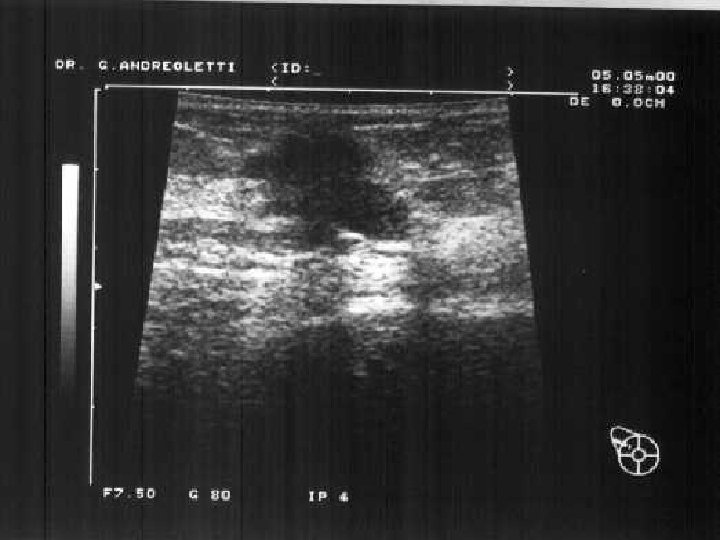

Ultrasound features of benign lumps: Respect tissue plains Long axis horizontal Wall clearly-defined Posterior brightness (cysts) Ultrasound features of malignant lumps Interrupt tissue plains Long axis vertical Wall irregular, poorly-defined Posterior shadowing